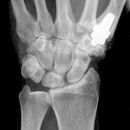

Bennett Fraktur mit geringer Dislokation